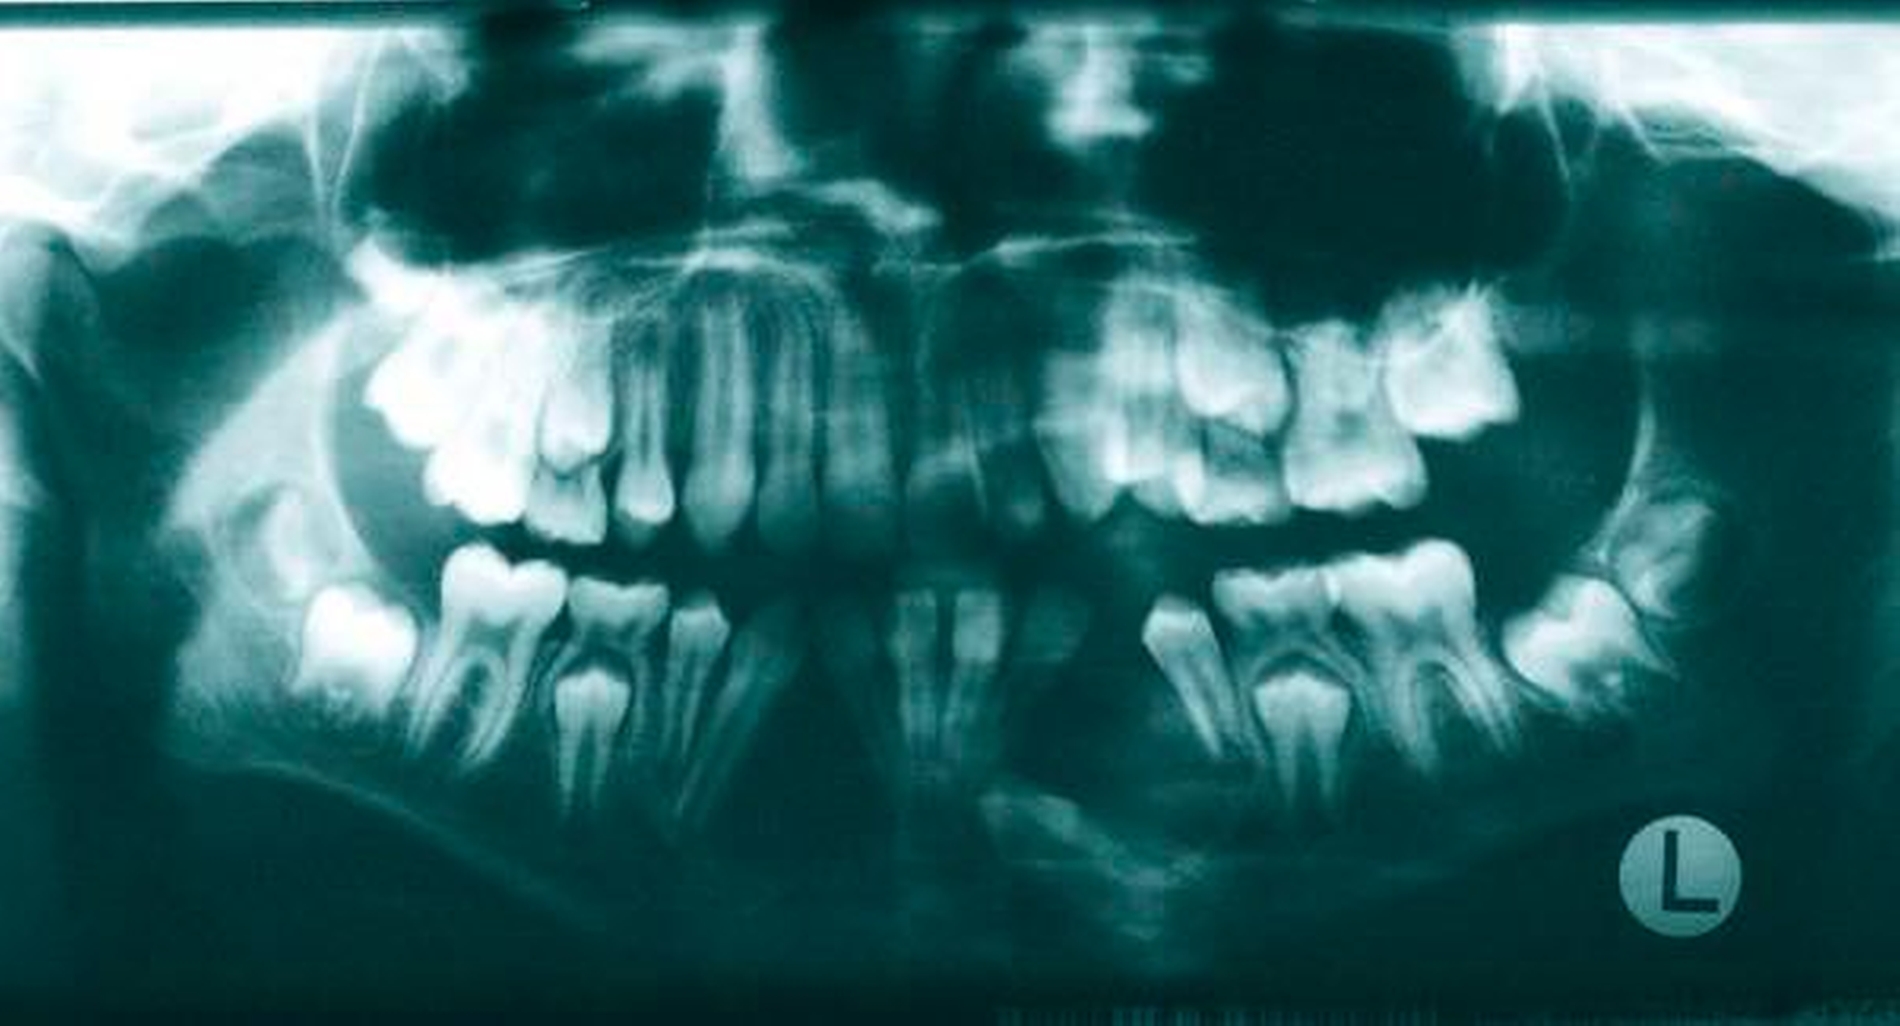

Radiologischer Befund

Im OPG (Abbildung 1) sowie in der DVT (Abbildungen 2 bis 5) imponieren zwei scharf begrenzte osteolytische Befunde im Bereich der anterioren Mandibula regio 34–32 und 41–43. Der retinierte Zahn 33 liegt basal im Lumen der Aufhellung.